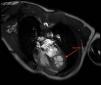

This is the case of a 33-year-old man from Morocco who sought consultation with a 3-month history of dyspnea and chest discomfort. An ultrasound (Fig. 1) identified the presence of a cystic mass in the apex of the left ventricle. Diagnosis was completed with an MRI, which characterized the cyst as hyperintense on T2-weighted images (Fig. 2). Symptoms of cardiac hydatidosis depend on the degree of pericardial and coronary compression, and the mass itself. Transthoracic ultrasound offers good sensitivity and specificity for diagnosis, which was confirmed by pathological anatomy during the intervention, which involved resection of vesicles with protection of the surgical bed using hypertonic scolicidal saline. Upon discharge, the patient remained on albendazole treatment for, at least, 6 months.

Figure 2